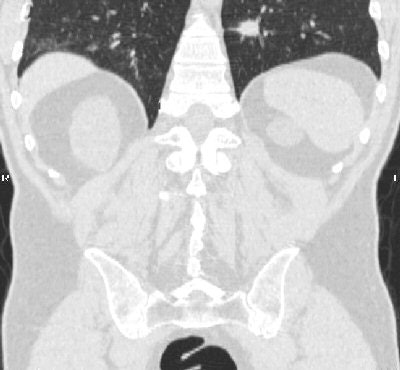

The mean age of patients with findings was 58.2 years, the same as the age of the cohort overall. Significant findings included three renal cell carcinomas, three lymphomas, and one bronchial adenocarcinoma, she said. (The lower lung is included in VC imaging to capture the entire colon.)

| A renal cell carcinoma (above) and a lung adenocarcinoma (below) are detected at screening VC of asymptomatic subjects. All images courtesy of Dr. Perry Pickhardt. |

![]() |